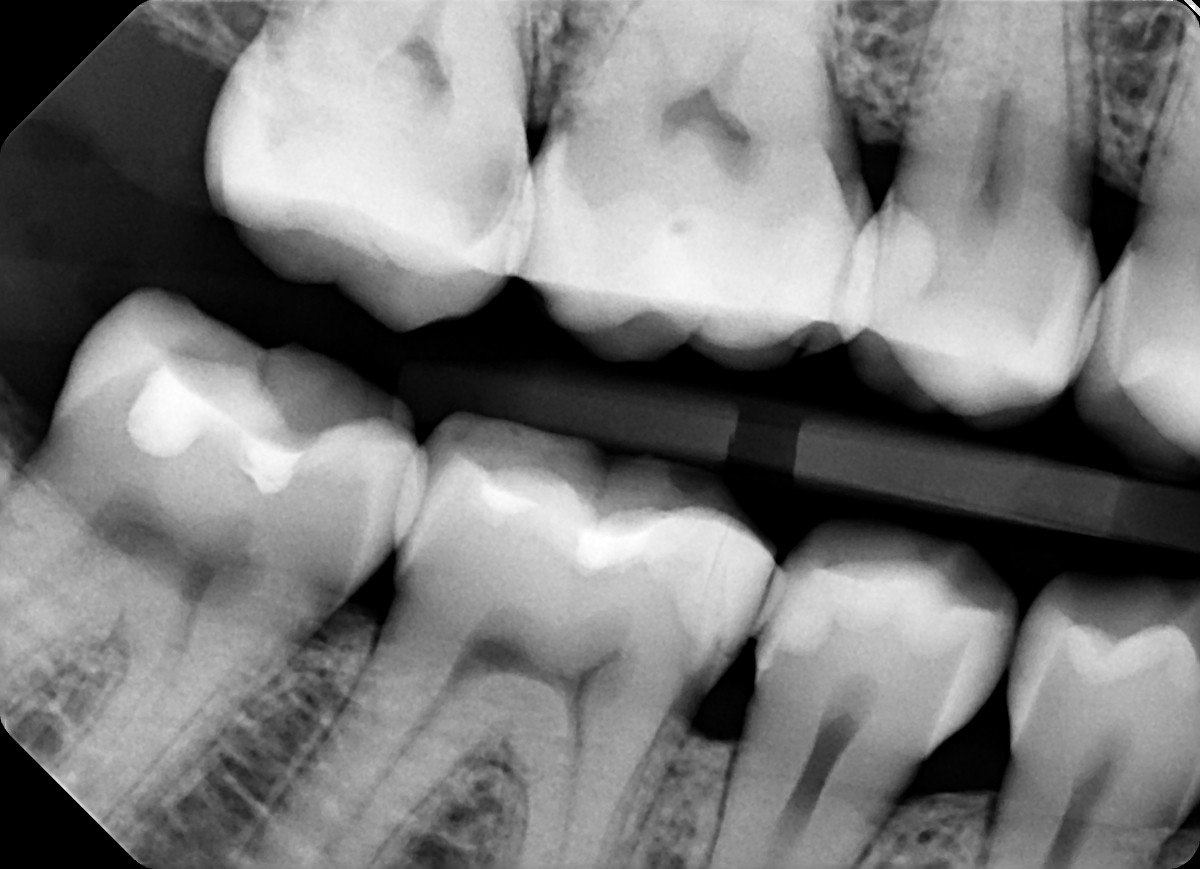

3. In the X ray bellow for which jaw periodontal bone loss is evident?